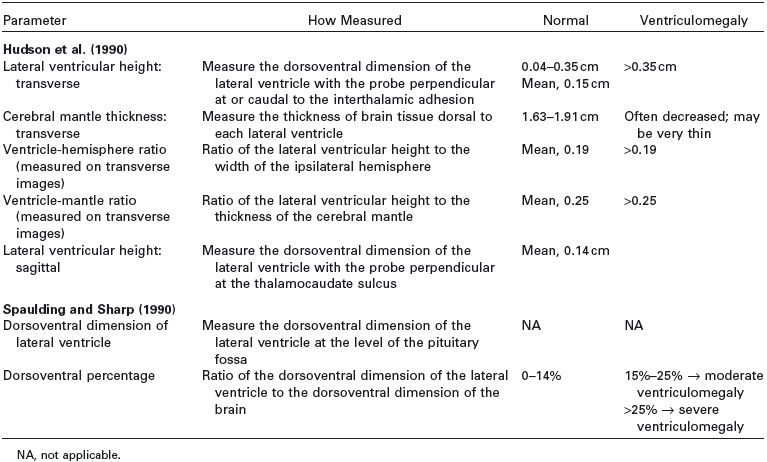

Table 1.1. Guidelines for measurements of the ventricular system as currently available in the literature

Several methods have been proposed for evaluating enlarged lateral ventricles on sonograms (Figure 1.10 and Table 1.1). The degree of ventriculomegaly ranges from the ventricles being only slightly enlarged to ventricles occupying most of the brain. Midline structures between the lateral ventricles are intact in some animals, but the lateral ventricles become confluent in others (Figure 1.11).

Several studies using ultrasonography or magnetic resonance imaging (MRI) have shown that the severity of clinical signs is not directly related to the degree of ventriculomegaly, and ventriculomegaly can be seen in neurologically normal dogs (De Haan et al. 1994; Vullo et al. 1997). A study using MRI to compare ventricular volume in Yorkshire terriers to that in German shepherds indicated that percentage of ventricle area to hemispheric area was significantly greater in the Yorkshire terriers, but the range of ventricle area for neurologically normal Yorkshire terriers overlapped that of neurologically abnormal Yorkshire terriers (Estave-Ratsch et al. 2001). Ventriculomegaly should not be equated with clinically significant hydrocephalus (Hudson et al. 1990; Spaulding and Sharp 1990; Ettinger and Feldman 2005). Breed differences and severity of clinical signs should be considered. Measurement of blood flow in the basilar artery might help to identify animals in which enlarged ventricles are significant or are likely to become clinically significant (Saito et al. 2003). In one study, RI at the basilar artery was higher in dogs with clinical hydrocephalus or other brain disease compared with normal dogs or dogs with asymptomatic hydrocephalus. Additionally, asymptomatic dogs with severe ventriculomegaly and high RI later developed clinical signs, although the use of high RI by itself did not identify asymptomatic dogs that were likely to become symptomatic (Saito et al. 2003).

Figure 1.10. Measurement of the lateral ventricles in a 3-month-old Chihuahua. A: Transverse sonogram at the level of the interthalamic adhesion showing measurement using the method of Hudson et al. (1990) The lateral ventricular height can be compared with the cerebral mantle thickness (the thickness of the parenchyma dorsal to the lateral ventricle) to obtain the ventricle-mantle ratio. B: Transverse sonogram at the level of the pituitary gland showing measurement by using the method of Spaulding and Sharp (1990). Another method of measurement calculates the dorsoventral measurement of the lateral ventricle as a percentage of the dorsoventral measurement of the brain. RLV, right lateral ventricle.